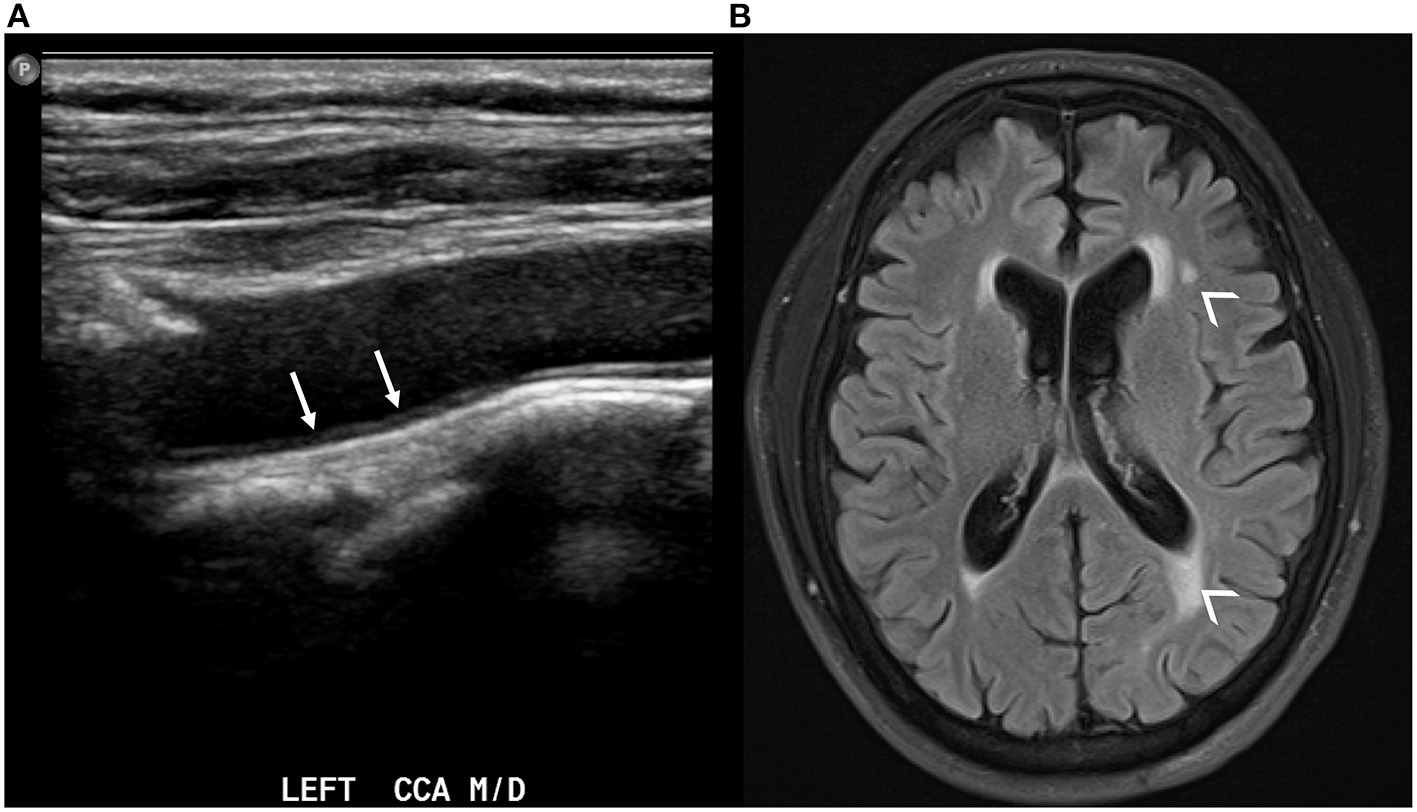

Figure 2

Carotid ultrasound demonstrating thickening of the intima-media in the left common carotid artery [(A), white arrows]. The same patient also has evidence of white matter hyperintensities in the periventricular white matter on axial T2 FLAIR brain MRI [(B), small arrowheads].